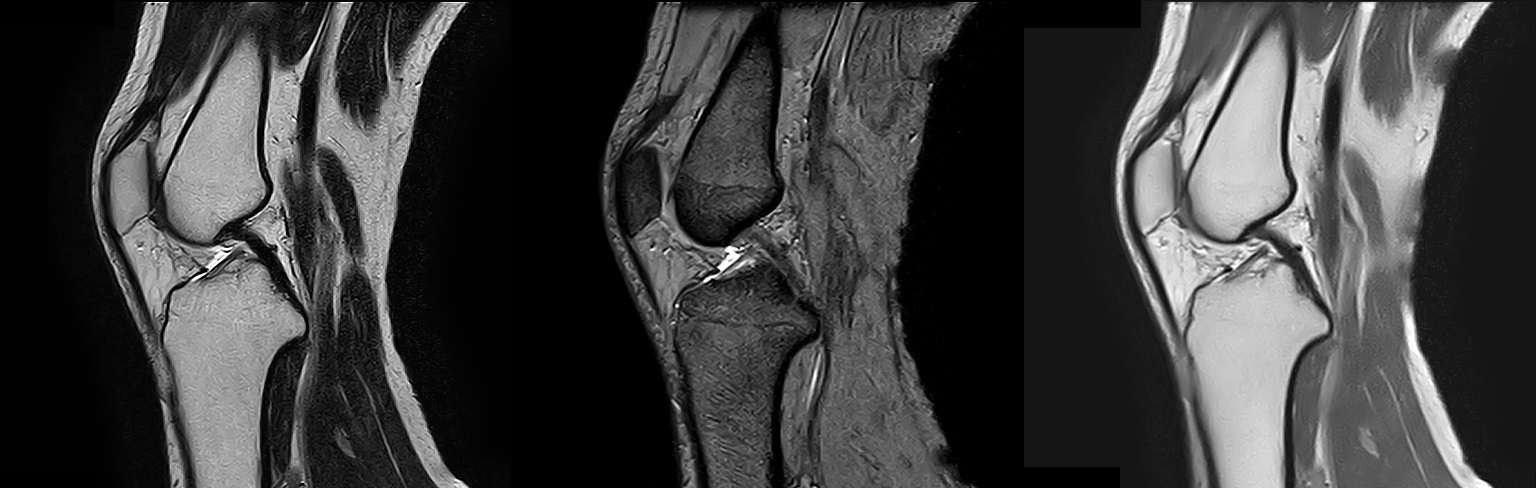

1.5TのMIR装置(富士フイルムヘルスケア株式会社製「MRイメージング装置 ECHELON Smart」)を導入し、以前よりも短い時間で高画質の撮像が可能になりました。

MRIは体内の断面像を縦、横、ナナメから人体に悪影響を与えずに見ることが出来る装置です。わずかな病変も見逃さない鮮明な画像は腫瘍などの早期発見や健診に威力を発揮します。薬品を全く用いずに血管撮影等が出来るので、患者さんは動かずに横になるだけで苦 痛なく精密検査が受けられます。

T2強調像 / T2*強調像 / プロトン密度強調像